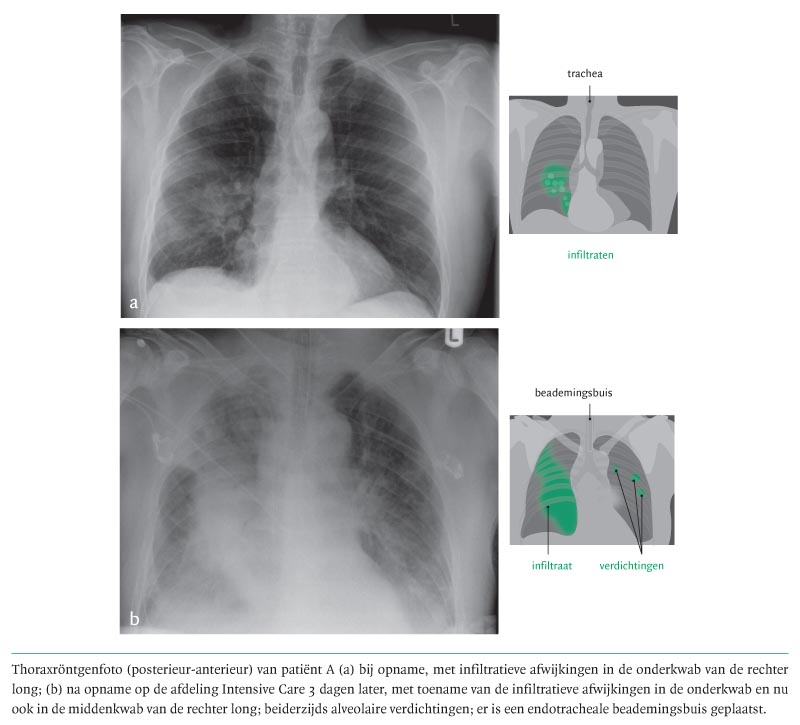

Een thoraxröntgenfoto toonde infiltratieve afwijkingen rechts, gelokaliseerd in de onderkwab (figuur a). Kweken van bloed, sputum, urine en feces, de Legionella-antigeentest in urine en serologisch onderzoek op Legionella en Mycoplasma hadden negatieve uitslagen. Ook influenzakeelkweken waren negatief.

Op de thoraxfoto na spoedintubatie was een toename van de infiltratieve afwijkingen in beide longen te zien (zie figuur b). Via de endotracheale tube werd een bronchoalveolaire lavage (BAL) verricht. Vanwege de anamnestische aanwijzingen voor een atypische pneumonie en onvoldoende effect van de initiële antibiotische therapie werd daarna gestart met doxycycline 200 mg 1 dd i.v. Gedurende 7 dagen werd vanwege de pneumonie en het daarop ontwikkelde ‘acute respiratory distress syndrome’ (ARDS) beademing in buikligging toegepast. Er ontstonden ECG-veranderingen met ST-elevaties in vrijwel alle afleidingen. Echografisch werd pericardeffusie geobjectiveerd als uiting van pericarditis. De serumwaarden van de hartenzymen waren niet-afwijkend. Er werd geen punctie verricht vanwege het ontbreken van hemodynamische consequenties van de pericarditis.